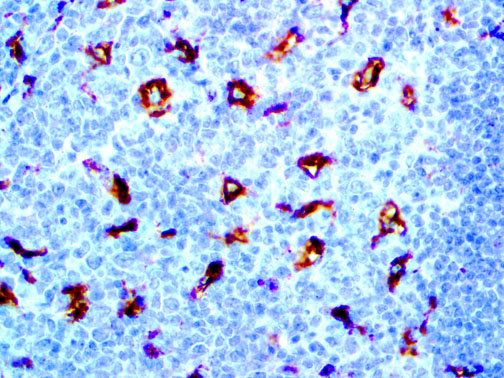

It is the ICU physician who is most likely to witness one of the deadliest manifestations of the abnormal immunological response, the cytokine storm syndrome (CSS). This response is also referred to by some as the cytokine release syndrome (CRS). CSS is characterized by continuous activation and expansion of macrophage and lymphocyte populations, which secrete large amounts of cytokines, causing the cytokine storm. This massive cytokine release is akin to hemophagocytic lymphohistiocytosis (HLH) disease, a syndrome characterized by initial unchecked and persistent activation of cytotoxic T lymphocytes and NK cells.

Clinical and laboratory manifestations of HLH include fever, enlarged liver and/or spleen, neurologic dysfunction, coagulopathy, liver dysfunction, cytopenias (i.e., low levels of erythrocytes, leukocytes, and/or platelets), hypertriglyceridemia, hyperferritinemia, hemophagocytosis, and eventually diminished NK cell activity as the immune system becomes progressively paralyzed. HLH can be familial (primary HLH) or secondary to another disease process (sHLH), such as rheumatic disease, in which it is referred to as macrophage activation syndrome (MAS, characterized by elevated ferritin).